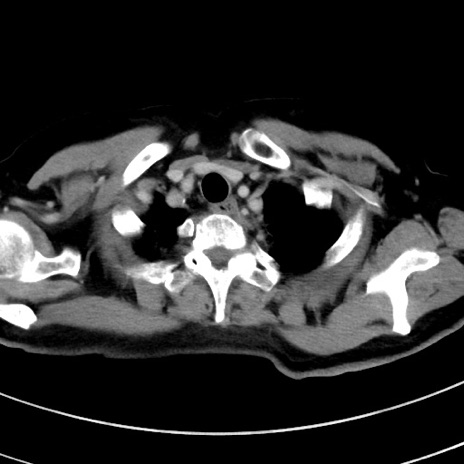

冠状断像

【症例】 60歳代女性

【主訴】むかつき、みぞおちの痛み

【現病歴】3日前よりむかつきがあり、食事がとれない。

【既往歴】糖尿病

【身体所見】発熱なし、心窩部圧痛軽度あるも、腹膜刺激症状なし。

【データ】WBC 7400、CRP 1.92